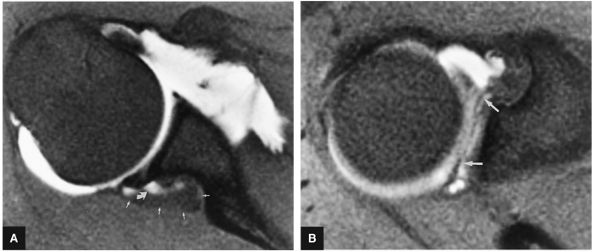

A separate FS PD-weighted FSE sequence is used to increase sensitivity to fluid and to identify paralabral cysts, articular cartilage labral avulsions, and muscle edema (Fig. 8.4). FSE sequences are less sensitive to intralabral signal intensity in the spectrum of degenerations or tears unless there is imbibed fluid. FSE (FS PD FSE) images, however, are superior for the demonstration of labral morphology in cases of avulsions or contour abnormalities.

without a FS PD FSE sequence to improve sensitivity for fluid and subtle labral tearing at the glenoid rim attachment.